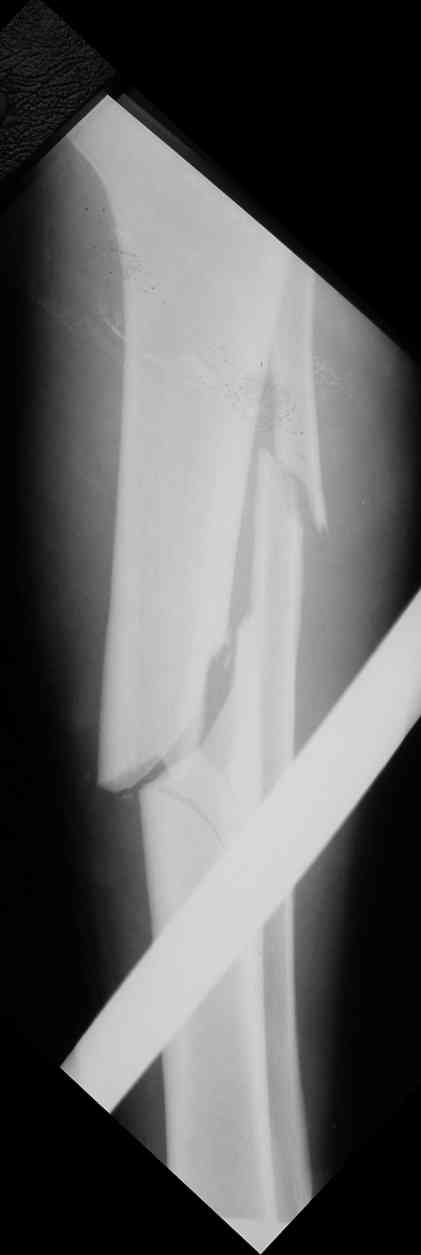

Дорогой Александр. Имею скромный опыт использования системы Fixion при

переломах плеча, бедра и тибии. Всего 18 наблюдений с сентября 2007

г.Результаты отличные. Гвоздь индивидуален для каждого медулярного

канала. Легко имплантируется как в узкий, так и в деформированный

канал. Это позволяет применять метод интрамедулярного остеосинтеза без

ненужных потерь времени операции, флюороскопии и реально снижает

крвопотерю и операционный риск. Удаление происходит без проблем.

Особенно интересны больные с ипсилатеральными переломами бедра и голени.

В отношении ранней нагрузки при спиральных переломах лучше не

торопиться. По данному случаю необходимо достигнуть исчезновения щели

между штифтом и внутреним кортексом по Rg. А так картинка прекрасная -

и длина сегмента и репозиция. Можно поздравить, коллега!